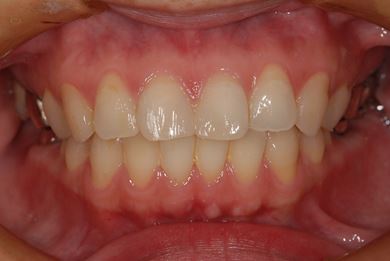

| 性別/年齢 | 女性 / 39歳 | ||||||||||||||||||||||||||||||||

| 主訴 | 右奥歯の虫歯と、右奥のインプラント治療について相談。 | ||||||||||||||||||||||||||||||||

| 治療方針 | 右下奥欠損部分をインプラント治療にて、機能的・審美的回復を行う。 | ||||||||||||||||||||||||||||||||

| 治療内容 | インプラント1本、ハイブリッドセラミッククラウン1本 | ||||||||||||||||||||||||||||||||

| 総治療費 | 329,963円 | ||||||||||||||||||||||||||||||||

| 治療期間 | 5ヶ月 |